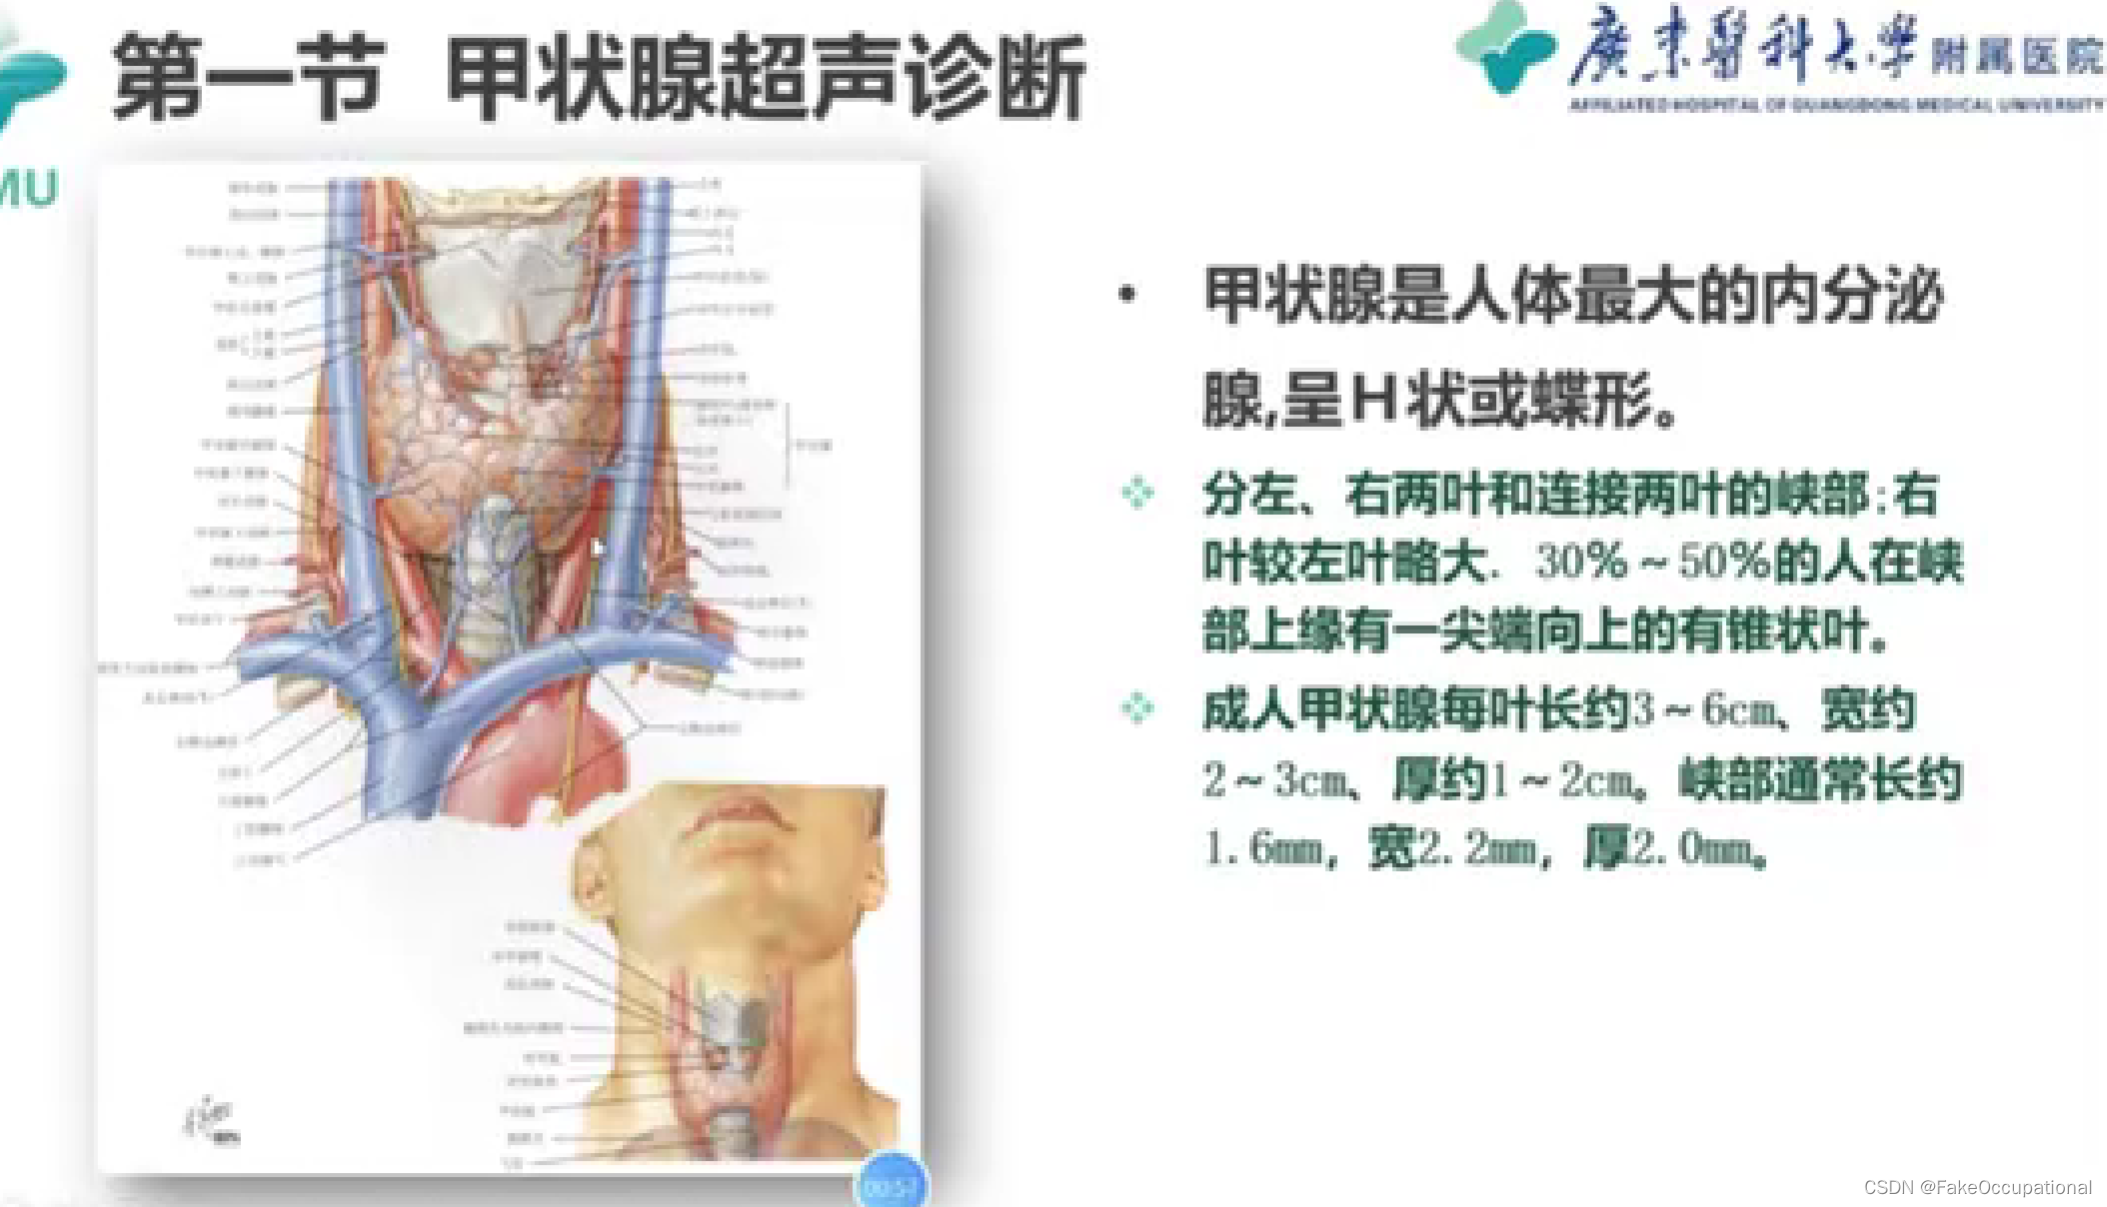

甲状腺超声